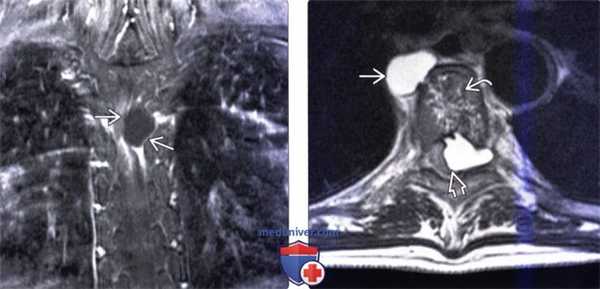

(Слева) Фронтальный срез, Т1-ВИ FS с КУ: контраструющееся по периферии образование позвоночника. Рецидив эхинококка является прогностическим фактором неблагоприятного прогноза заболевания, частота которого достигает 30-100%. До 40% рецидивов возникают в течение первых двух лет после первичной операции.

(Справа) Аксиальный срез, Т2-ВИ: признаки эхинококкового поражения среднегрудного позвонка. На передней поверхности позвонка сформировалась сферической формы киста. Разрушение задней покровной пластинки привело к распространению кисты в эпидуральное пространство и тяжелому сдавлению спинного мозга.